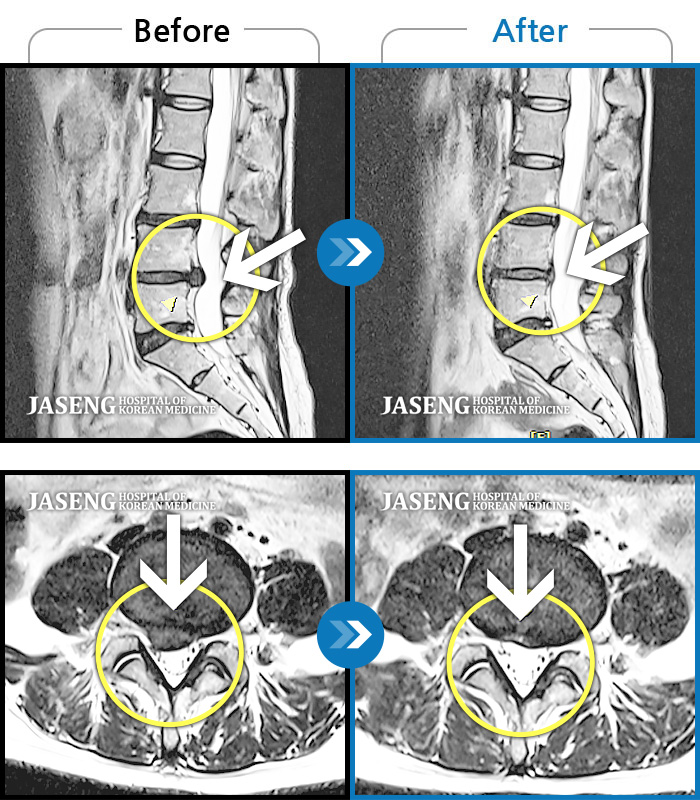

허리디스크

광주 · 김동은 원장

좌측 골반 및 종아리부터 발까지 이어지는 저림과 통증으로 내원하셨습니다.

촬영시기

2023.10.03 ~ 2025.08.14

2025.08.22

조회수 268